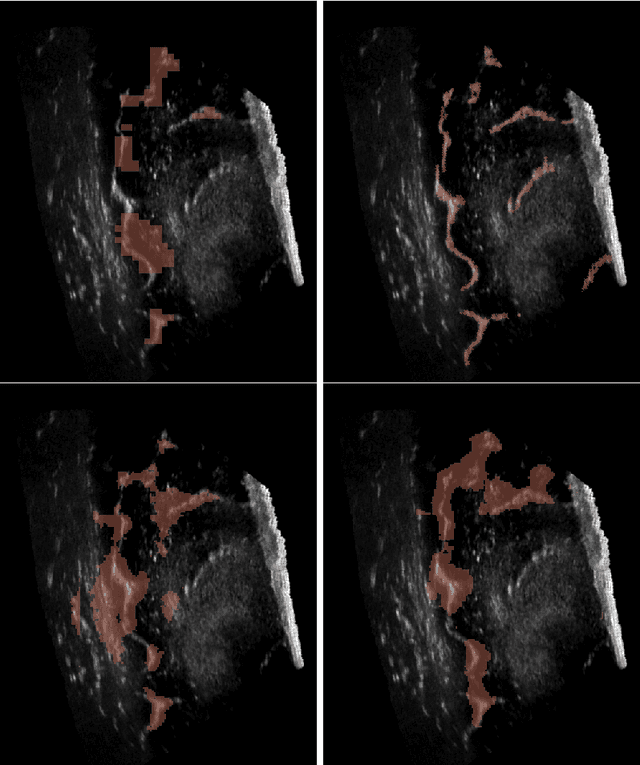

Abstract:Freehand three-dimensional ultrasound (3D-US) has gained considerable interest in research, but even today suffers from its high inter-operator variability in clinical practice. The high variability mainly arises from tracking inaccuracies as well as the directionality of the ultrasound data, being neglected in most of today's reconstruction methods. By providing a novel paradigm for the acquisition and reconstruction of tracked freehand 3D ultrasound, this work presents the concept of Computational Sonography (CS) to model the directionality of ultrasound information. CS preserves the directionality of the acquired data, and allows for its exploitation by computational algorithms. In this regard, we propose a set of mathematical models to represent 3D-US data, inspired by the physics of ultrasound imaging. We compare different models of Computational Sonography to classical scalar compounding for freehand acquisitions, providing both an improved preservation of US directionality as well as improved image quality in 3D. The novel concept is evaluated for a set of phantom datasets, as well as for in-vivo acquisitions of muscoloskeletal and vascular applications.